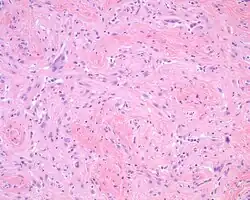

The overlying skin or squamous mucosa is intact and uninvolved by the process. There is normal glial tissue set within a fibrous connective tissue stroma. There is such blending, that the underlying process may be difficult to detect without special studies. In a few cases, large gemistocytes, neurons, choroid plexus, ependyma, and retinal pigmented cells may be seen.[2][3]

A trichrome stain will highlight the dual components well, with the glial tissue staining red, while the background fibrosis stains a bright blue.[2]

The glial tissue is highlighted with S100 protein and with glial fibrillary acidic protein, although the latter is much more sensitive for glial tissue.[2]